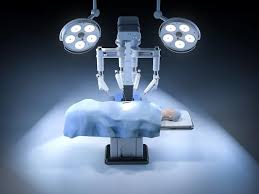

Introduction to Robotic Orthopedic Surgery Robotic orthopedic surgery in Kanker offers a modern and highly precise approach to treating complex bone and joint conditions. Orthopedic problems such as arthritis,...

Introduction to Robotic Joint Replacement Robotic joint replacement in Kanker represents a major advancement in orthopedic surgery, offering higher precision, improved outcomes, and faster recovery compared to traditional techniques....